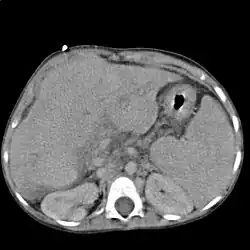

Диагностика

Расширенные и извитые венозные коллатерали выявляются при ангиографии, компьютерной томографии, ультразвуковом исследовании или в ходе оперативного вмешательства.